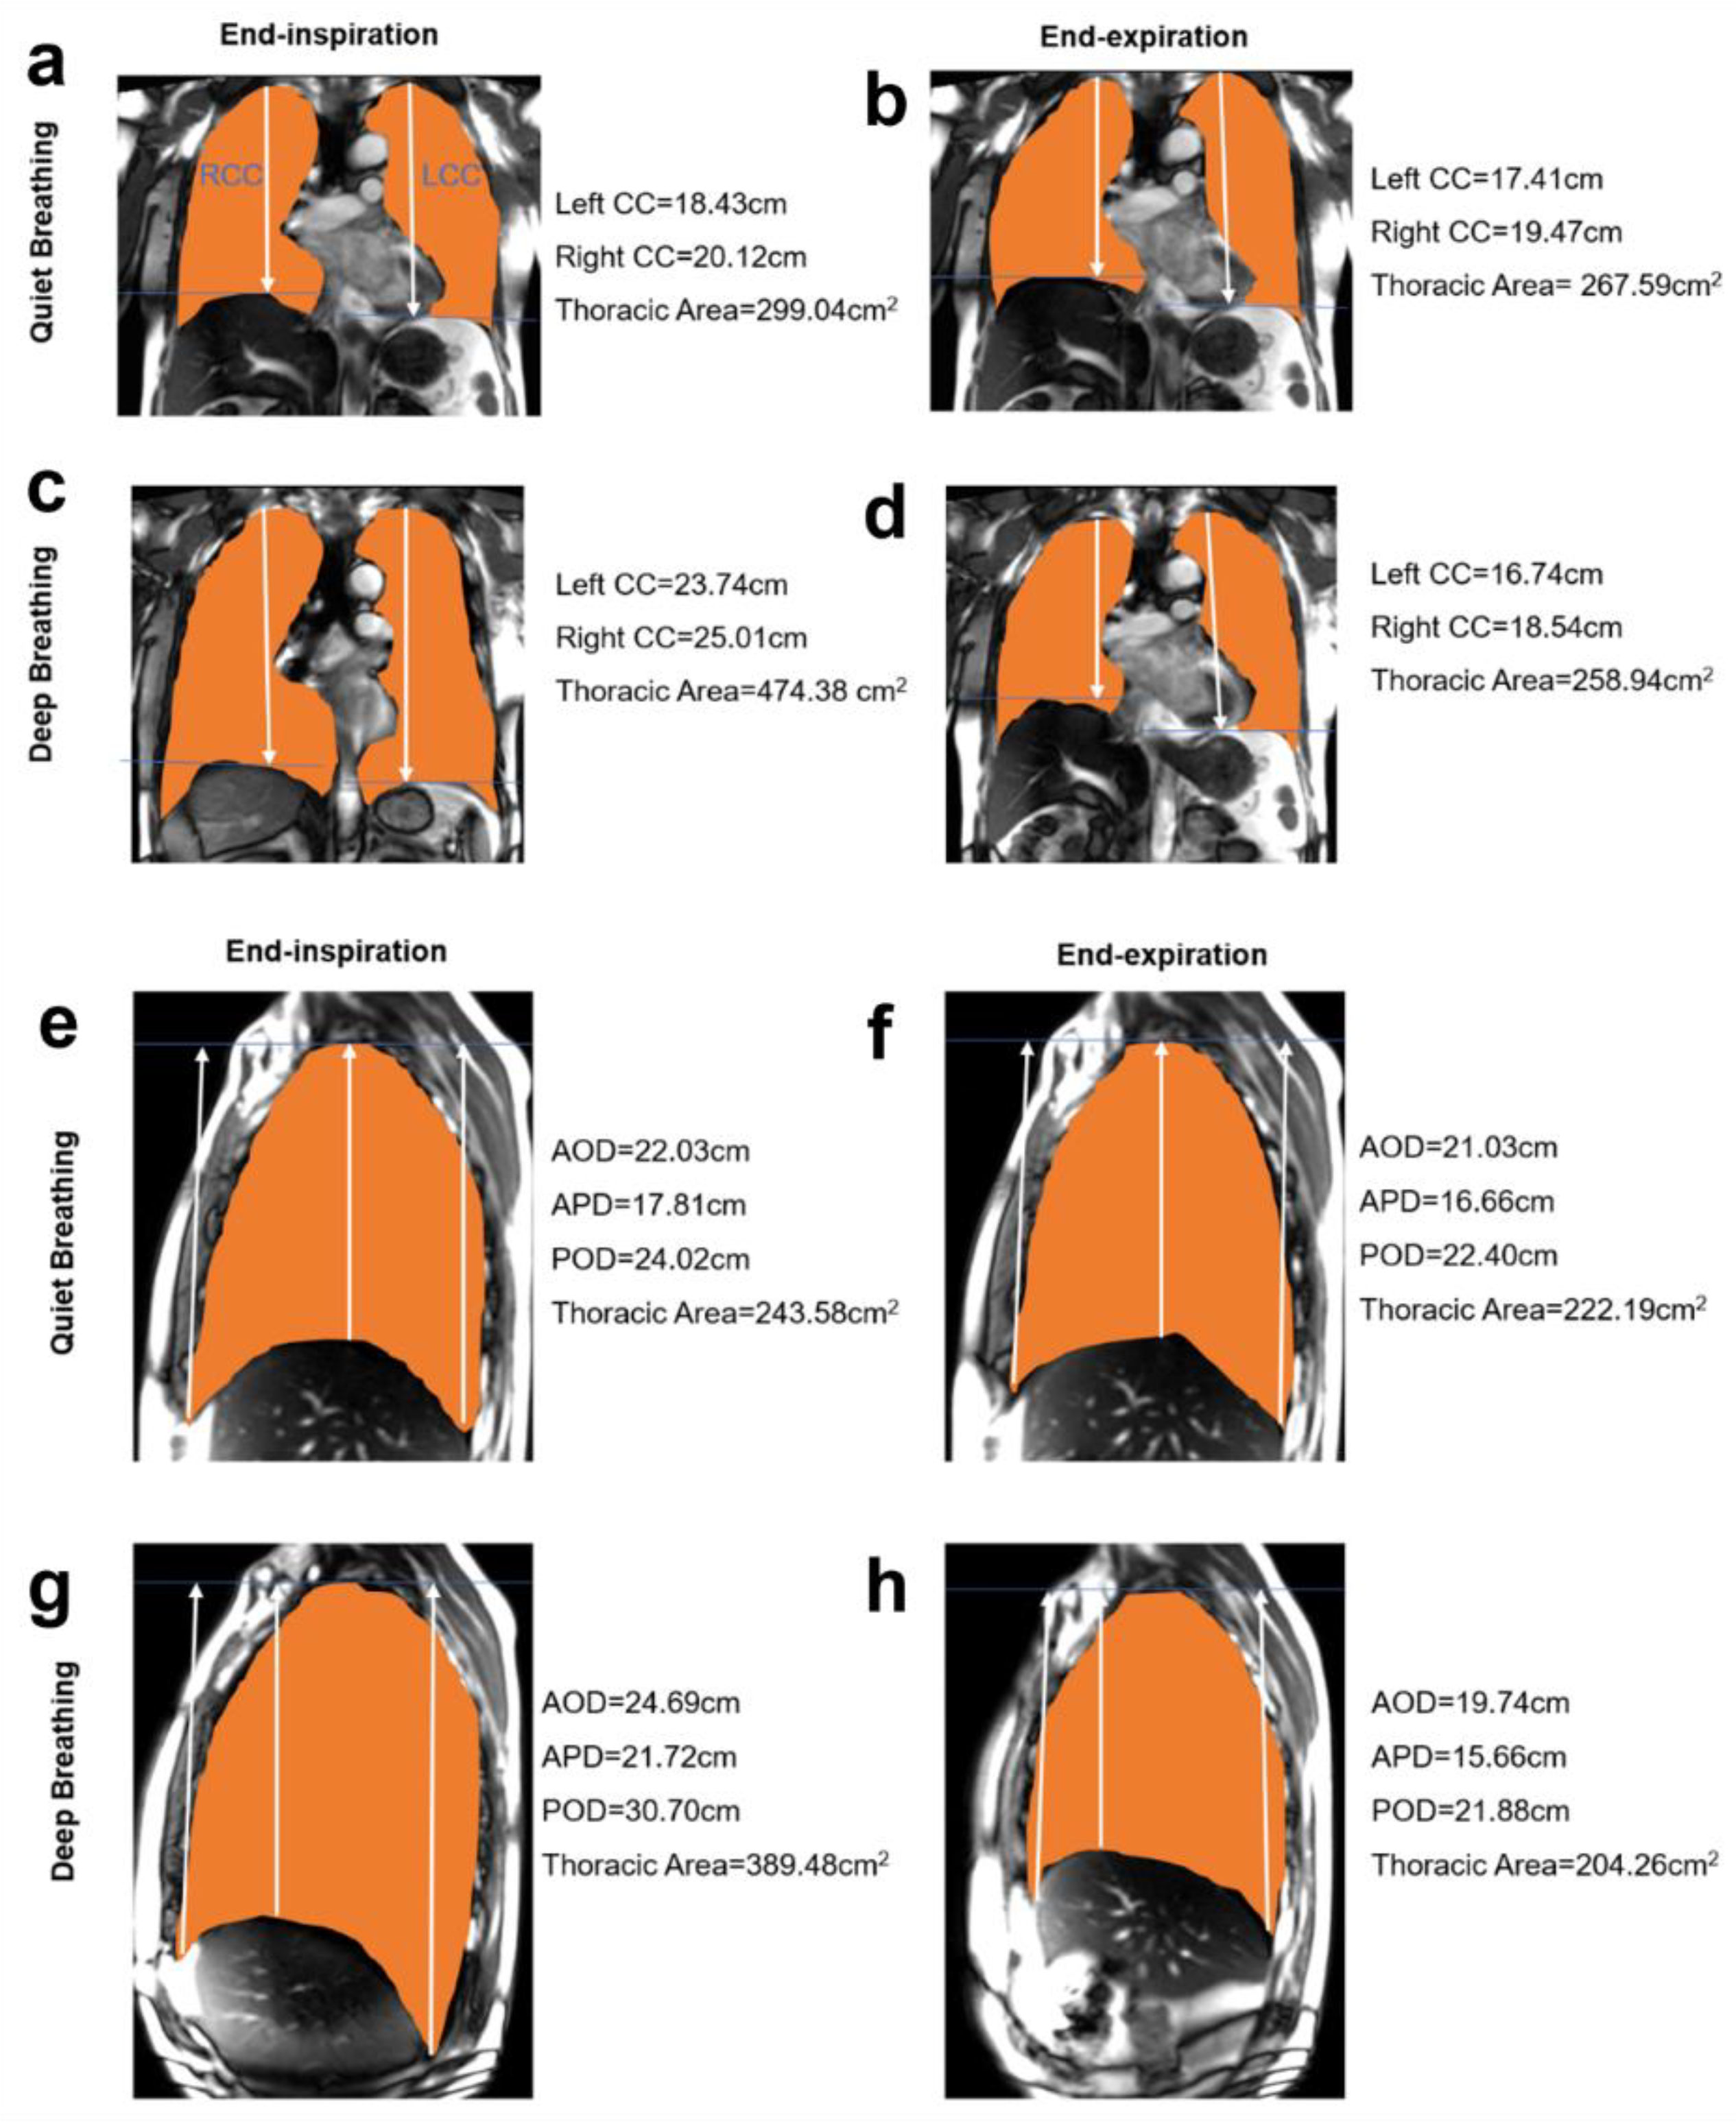

2.4. MR Image Processing and Measurements

3.2. Quantitative Analysis of Chest Wall and Diaphragmatic Motion